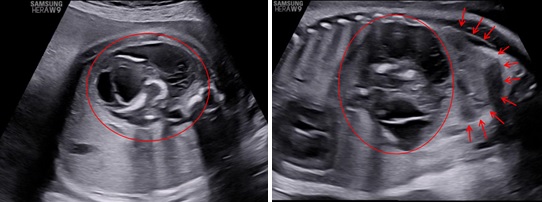

Siêu âm bé sau sinh tại bệnh viện Nhi đồng 1 ghi nhận ở vùng sau phúc mạc bên trái có một khối không đồng nhất kích thước: 53x81x75mm với hình ảnh vòm sọ, cột sống, mô mở và xương dài bên trong và đẩy thận trái xuống hố chậu. Siêu âm chẩn đoán: Thai trong thai.

Hình 5: Siêu âm em bé sau sinh, ở sau phúc mạc và trên thận có một khối không đồng nhất với hình ảnh vòm sọ (dấu sao) và cột sống (mũi tên)